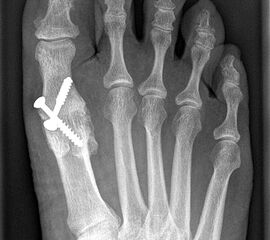

Das nachfolgend präsentierte OP-Verfahren zeigt die Großzehengrundgelenkarthrodese mit Gelenkflächenpräparation mittels sogennanter „Cup-and-Cone“-Fräsen und einer dorsal angebrachten variablen winkelstabilen Platte mit Gleit-/Kompressionsloch.

• Evtl. 3,5 bis 4,5 mm (durchbohrte) Schrauben (plantare Zugschraube)

Gekreuzt eingebrachte Schrauben werden immer noch als kostengünstige Standardtechnik der Osteosynthese beschrieben und können bei kräftigen und stabilen Knochenverhältnissen und entsprechender Erfahrung prinzipiell verwendet werden 141516. Der Einsatz kanülierter Schrauben unter Durchleuchtung erleichtert die Operation.

Durch die Verwendung sogenannter „Cup-and-Cone“-Fräsen und die Osteosynthese mit winkelstabiler Platte ggf. in Kombination mit einer interfragmentären Zugschraube kann die Rate der Pseudarthrosen vor allem bei schlechten Knochenverhältnissen deutlich reduziert werden, sodass dieses Verfahren zunehmend empfohlen wird 9.